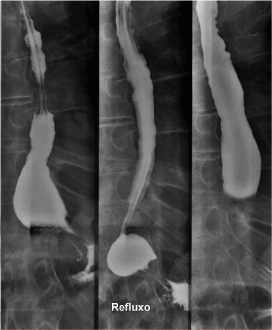

Due to the appearance of dysphonia and aggravation of dysphagia, he was admitted. Patient presented malnourished and dehydrated, with muscle flaccidity, cervical and axial skeletal rigidity. Another UDE was performed (Figure 3), which showed a bulge in the hypopharynx due to external compression – dysphagia lusoria. Computed Tomography (CT) (Figures 4 and 5) presented degenerative alterations affecting the cervical vertebrae with osteophytosys, reduction of discal spaces, subchondral cysts and anterior bridges syndesmotic. At the C3-C4 level, there was a large anterior osteophyte, which compressed the upper esophagus at the level of the vestibular fold (Figures 6,7 and 8). Due to malnutrition and repetitive aspiration pneumonias, feeding was started through a nasoenteral tube. Patient was referred for orthopedic surgeon to perform definitive treatment with resection of the cervical osteophyte.

Figure 4. Computed Tomography: diffuse skeletal hyperostosis

Figure 5. Computed Tomography: diffuse skeletal hyperostosis